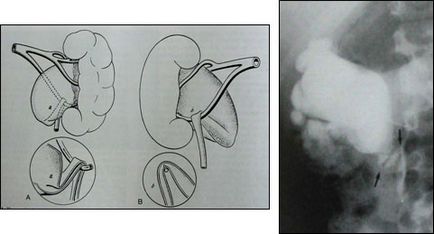

B. Compression lumen uréter külső (extrinsic) metsző a hajó, vagy egy további edényben nizhnepolyarnym vese (2. ábra), a tumor infiltrációt (gyulladás a retroperitoneum)

2. ábra. Kompressziós aberráns ureter (elutasított) a hajó